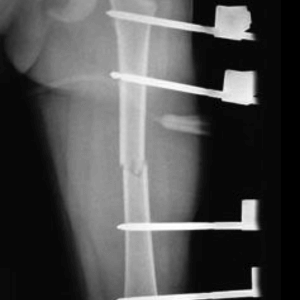

Femoral Shaft Fractures